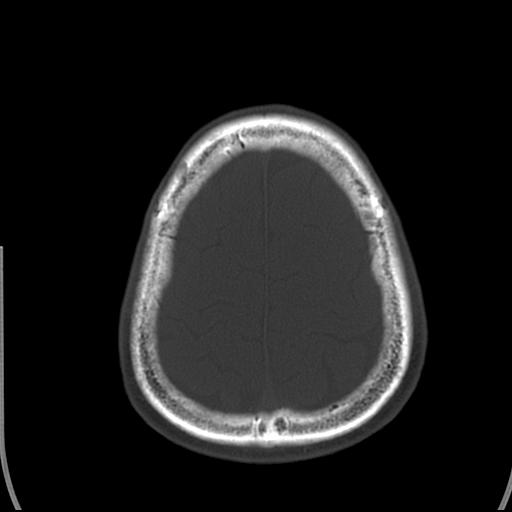

标题: CT25435:头皮下高密度影???

头皮下高密度结节影???临床上在老年男性比较常见。大家看看是什么?成因是? 本例患者,男性,51岁。外伤来诊。无染发史及发根植入史。

考虑异物。

皮下钙化点

这种东西有时要结合触诊和望诊。